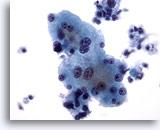

画像 4

肝FNA – 良性肝細胞

反応性変化を来した肝細胞。核は大小不同で、二核を有しています。

40倍

画像 4

肝FNA – 良性肝細胞

反応性変化を来した肝細胞。核は大小不同で、二核を有しています。

40倍